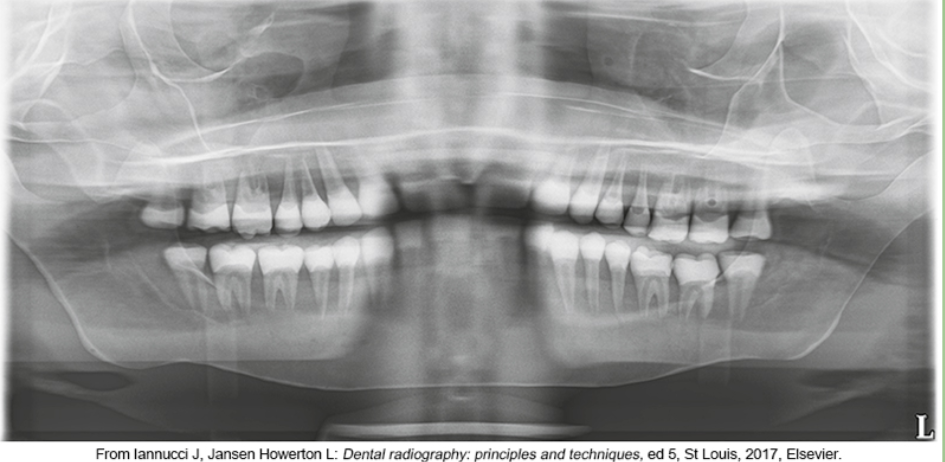

whats the problem

chin too high